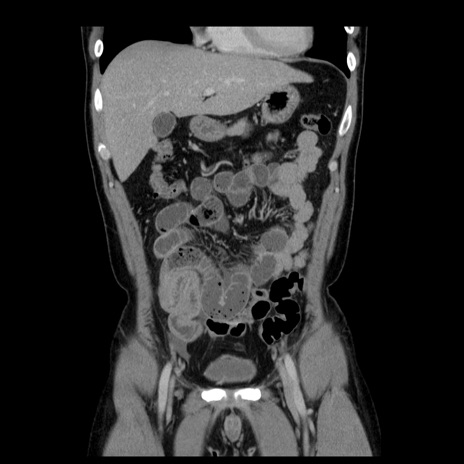

横断像